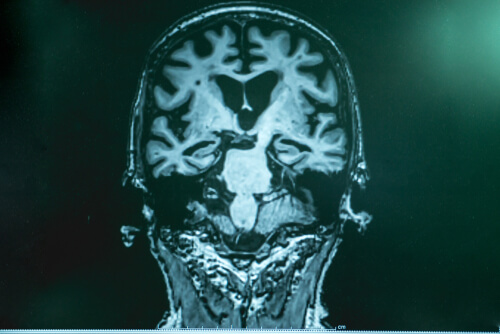

El doctor Lopera explica que en el alzhéimer hay una especie de acumulación de “basura” en el cerebro. La misma está compuesta por una proteína llamada amiloide. Los fragmentos de esta se unen y forman algo así como un “pegote” que se adhiere a las neuronas y causa una cascada de fallas. La otra parte de “basura” es el tau, que envuelve la neurona, la encierra y la mata. El Tau es más nocivo.